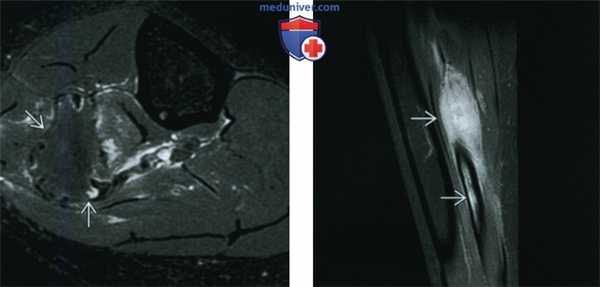

(Слева) МРТ, аксиальная проекция, режим Т2, с подавлением сигнала от жира: у этого же пациента определяется область преимущественно низкоинтенсивного сигнала, окруженная зоной умеренно выраженного отека. Низкоинтенсивный сигнал занимает большую часть патологического очага. Десмопластическая фиброма является внутрикостной формой фиброматоза или мягкотканного десмоида. Такое новообразование встречается редко, его наличие можно предполагать при умеренно агрессивном костном очаге, большая часть которого имеет сигнал низкой интенсивности в режиме Т2.

(Справа) МРТ, сагиттальная проекция, режим Т1, с подавлением сигнала от жира и контрастированием, этот же пациент: очаге контрастным усилением.

• МРТ позволяет установить диагноз; эффективна для оценки зоны опухолевого поражения

• Режим Т1: низкая интенсивность сигнала (изо- или гипоинтен-сивный по отношению к мышце)

• Последовательности, чувствительные к жидкости (с подавлением или без подавления сигнала от жира): изо- или гипоинтенсивный сигнал по отношению к мышце:

о Сигнал низкой интенсивности в режиме Т2 охватывает не менее 50% очага

о Сигнал низкой интенсивности в режиме Т2 является наиболее значимым дифференциально-диагностическим признаком

о Может искажаться на фоне отека и кровоизлияния в зоне патологического перелома

• Контрастное усиление: неоднородное накопление контраста